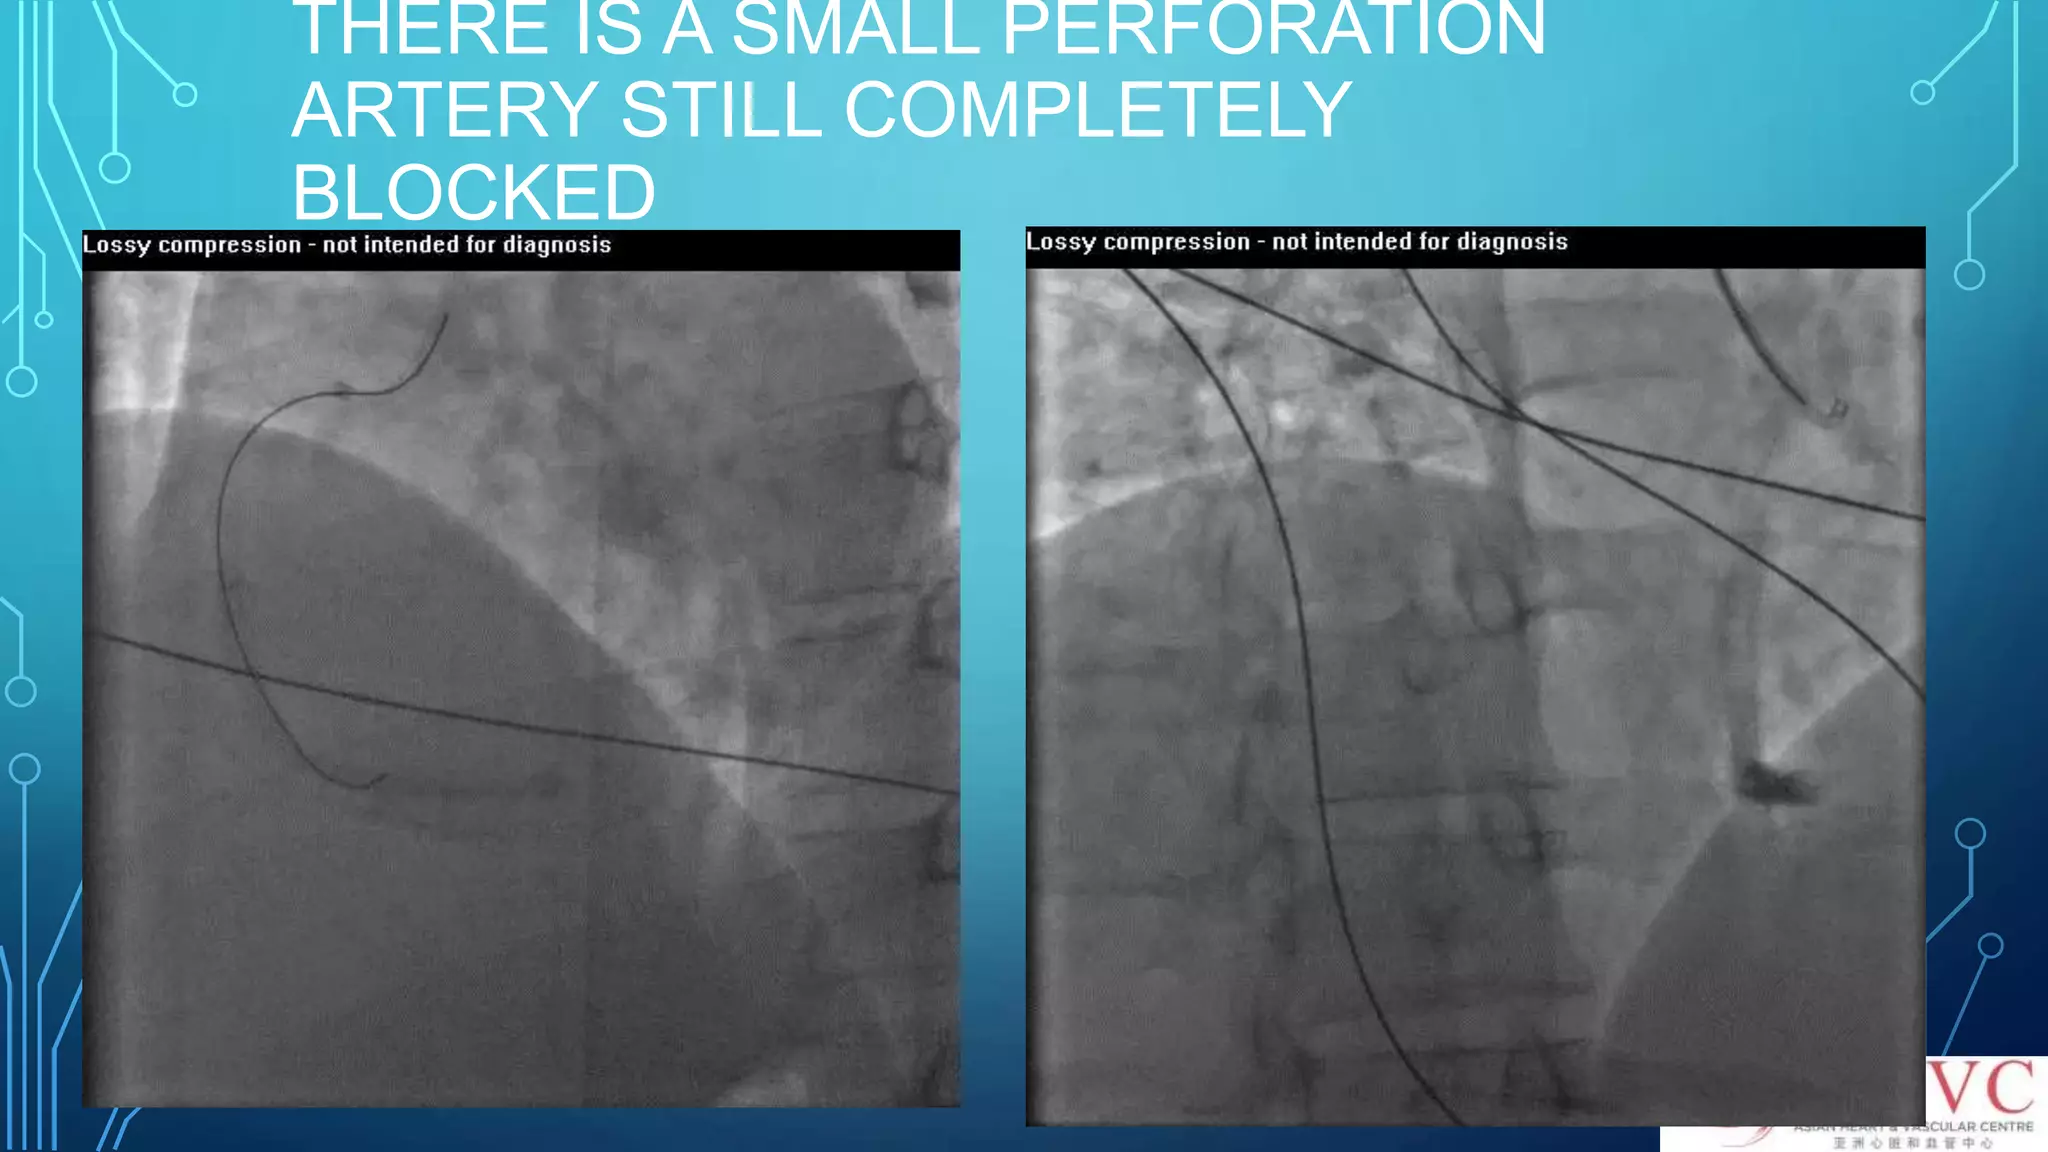

WHAT ELSE CANGO WRONG WITH INEXPERIENCE DOCTOR?When the CTO segment is not correctly crossed by wire

NOT KNOW WHATTO DO SO PLACED A STENT

THERE IS ASMALL PERFORATION ARTERY STILL COMPLETELY BLOCKED

PUTTING A STENTIN SUB-INTIMAL SPACE WILL COMPLETELY BLOCK UP THE LUMEN! Lumen occluded! Game Over!